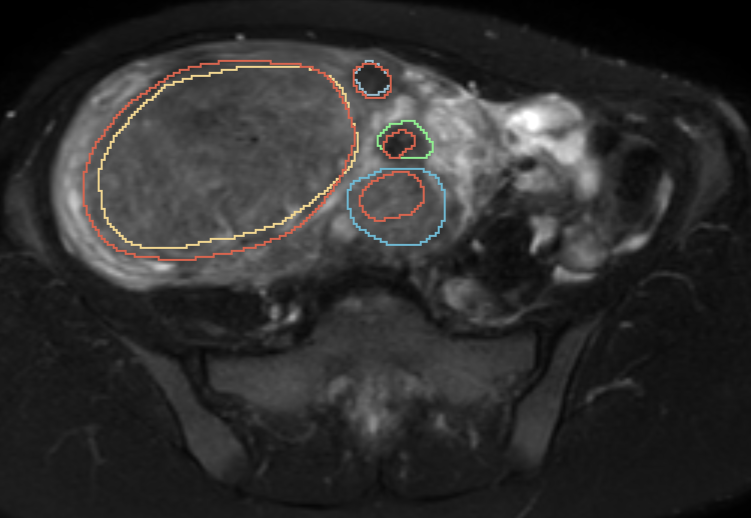

The MSI is able to adapt to different clinical applications by the modification of the il and ol hyperparameters. A representative example is shown in Fig. 11. The MSI was calculated with the default il=1\texttt{il}=1, ol=1\texttt{ol}=1 hyperparameters, as well as with il=5,10\texttt{il}=5,10 and ol=5,10\texttt{ol}=5,10. The traditional metric values are also indicated. If there are no special needs, the value of 0.857 could be clinically relevant, which is in agreement with the traditional metric values. In contrast, if we would want to measure the volumes of the fibroids for treatment, the inner deviation had more severe consequence. That is why the segmentation of this slice should have a low score (0.512 or 0.392). If the outer deviation would have more clinical impact, MSI value of 0.733 or 0.626 could be achieved. The MSI values with ol=5,10\texttt{ol}=5,10 are still larger than the MSI values with il=5,10\texttt{il}=5,10, because the segmentation has more inner alterations than outer.

Refer to caption

Figure 11: Representative slice with reference and test fibroid contours. The reference contours are shown with yellow, green, purple and blue colors, the test contour is shown in red. The corresponding traditional metric values (Dice and Jaccard index, average Hausdorff distance) and the MSI values with different hyperparameters are shown in Table 1.

MSI contour1 contour2 contour3 contour4 il ol

0.858 0.813 0.906 0.902 0.759 1 1

0.734 0.813 0.906 0.178 0.654 1 5

0.626 0.813 0.906 0.037 0.440 1 10

0.512 0.117 0.278 0.898 0.746 5 1

0.392 0.012 0.070 0.897 0.713 10 1

Table 1: MSI values with different il and ol hyperparameters for the representative slice of Fig. 11. The first column shows the MSI values for the representative slice. In the contour1, 2, 3, 4 columns, the MSI values for the individual contours are indicated. The il=1, 5, 10 and ol=1, 5, 10 was used.